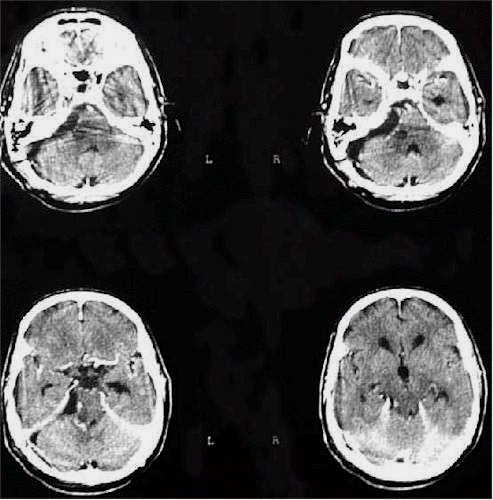

La stereotassia, metodica sviluppata prima dell’avvento della neuronavigazione, prevede tradizionalmente l’applicazione al capo del paziente di una struttura meccanica rigida, denominata casco stereotassico

(stereotassia frame-based). A tale struttura vengono associati specifici sistemi di riferimento che consentono al paziente di eseguire esami di imaging quali Risonanza Magnetica, Tomografia Computerizzata o angiografia.

Accanto alla stereotassia classica con casco rigido, oggi è disponibile anche la

stereotassia frameless, che non richiede l’applicazione di una struttura rigida al capo. In questa modalità, la localizzazione del bersaglio avviene mediante sistemi di riferimento esterni o cutanei e tecnologie di localizzazione spaziale computer-assistita, mantenendo un’elevata accuratezza e offrendo maggiore flessibilità procedurale e comfort per il paziente.

Attraverso tali metodiche è possibile ottenere coordinate operatorie tridimensionali che consentono di raggiungere il bersaglio chirurgico con precisione millimetrica. Anche in questo caso l’intervento viene pianificato accuratamente, identificando la lesione e selezionando la via di accesso più sicura per il paziente.

Un ulteriore vantaggio chirurgicamente rilevante della stereotassia è la possibilità di acquisire una rappresentazione tridimensionale della lesione, collocata all’interno di un preciso sistema di coordinate spaziali.

Nonostante il recente avvento della neuronavigazione, che ha semplificato questo tipo di approccio soprattutto nella patologia tumorale, la stereotassia — sia frame-based sia frameless — rimane tuttora di grande utilità nei casi in cui sia richiesta una accuratezza estremamente elevata, in particolare per lesioni profonde e circoscritte.